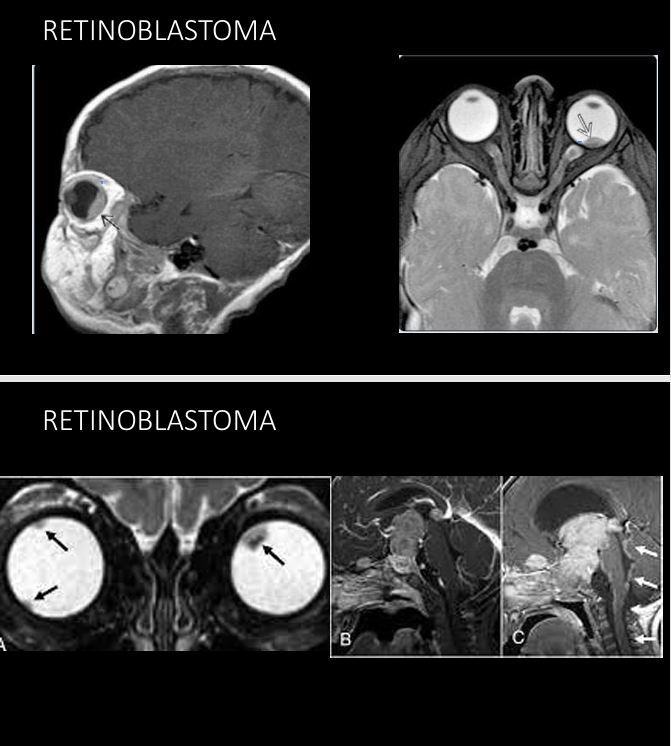

Definición Retinoblastoma

Tumor maligno primario de la retina

Trilat o cuadrilat - arriba de silla turca o pineal

Clínica retinoblastoma

Leucocoria

Pérdida visión

Estrabismo

18 meses

Imagen en retinoblastoma

Calcificaciones intraoculares

TC- ver calcificaciones

RM - mapeo tumor

USG - lesión hiperecogénica con calcificaciones

RM en retinoblastoma

Evaluar implicaciones intra y extraoculares / intracraneales

Hemorragia retinal